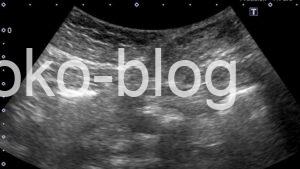

おや、皮下に何かが…

拡大してみました。うーん?

腹部用の設定ではないのでわかりづらいですが、腸管と連続しているように認めます。

腸管が皮下に見えるってことはヘルニアかな、カラーものらないから嵌頓の可能性もあるかなと医師に報告。